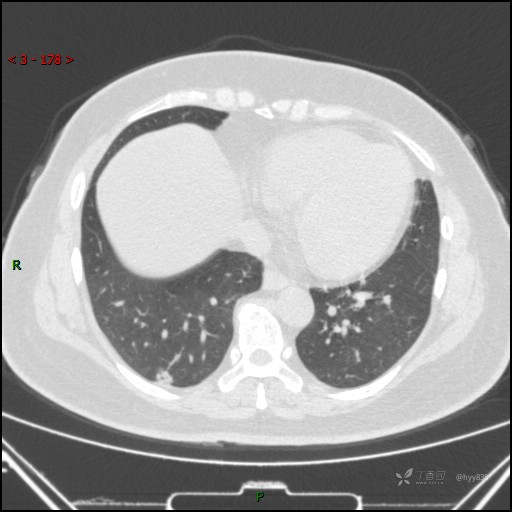

51岁/F,体检发现肺结节,又见“鬼脸”,增强也有特点,请分析---结果公布~

简要病史:体检发现右下肺结节,来我院行进一步增强检查并手术

胸部CT平扫